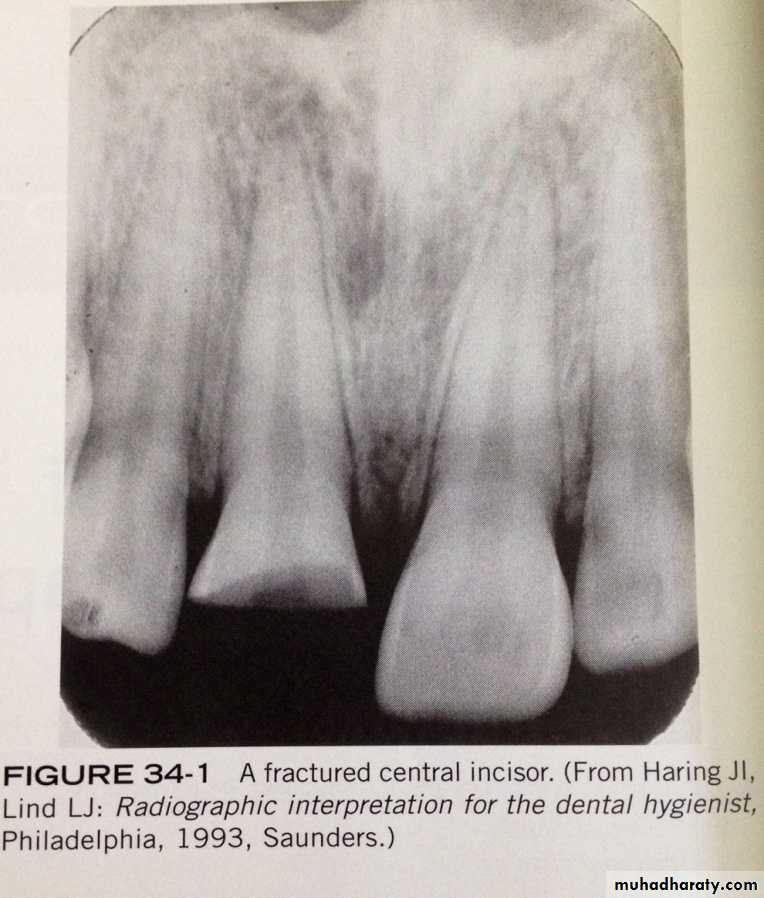

Fractures that effect crown most often involve the anterior teeth. Most crown fractures result from an accident involving a fall or a motor vehicle.Root fractures:

- Root fractures are less common than crown fractures.- Root fractures occurs most often in the maxillary central incisor region.

-if the x-ray beam is parallel with the plane of the fracture, the root fracture appear as sharp radiolucent line on a periapical radiograph